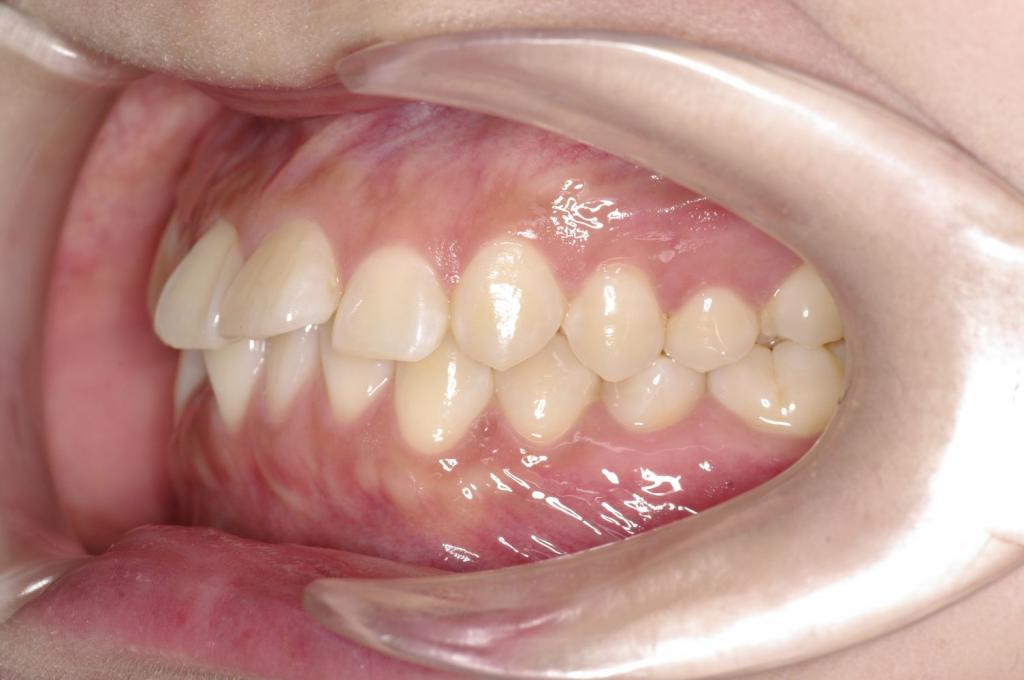

前歯、出っ歯・開咬の矯正治療

(治療期間、治療前後写真、治療方法、費用)WORKS